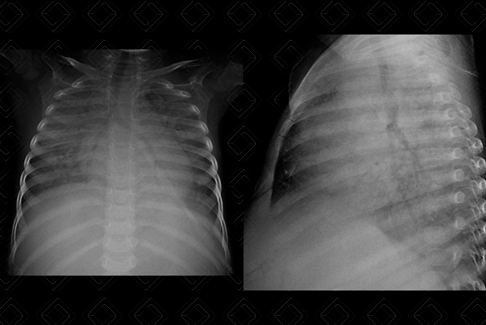

Texto alternativo para a imagem Figura 2. Créditos: Dra. Elazir Mota - Rio de Janeiro/RJ

Descrição da figura 2: Estudo do mesmo paciente foi complementado com Tomografia computadorizada do tórax, evidenciando extensas opacidades em vidro fosco associado a espessamento liso dos septos interlobulares. O diagnóstico foi confirmado por exame citopatológico do lavado broncoalveolar.

• Tomografia computadorizada do tórax: Na TC, os achados mais comuns incluem opacidades em vidro fosco com distribuição geográfica e espessamento liso dos septos interlobulares que, associados, resultam no padrão de pavimentação em mosaico (figura 2).